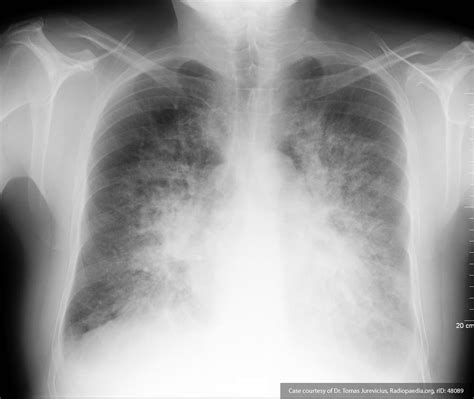

• Bat-wing Opacities: In more severe cases, bilateral central alveolar opacities sparing the periphery of the lungs, indicating profound alveolar flooding.

Differentiating Cardiogenic from Non-Cardiogenic Edema

While the Pulmonary Edema Cxr is excellent at confirming the presence of fluid, determining the etiology is equally important. Cardiogenic pulmonary edema is typically associated with a widened cardiothoracic ratio (cardiomegaly) and vascular redistribution. In contrast, non-cardiogenic pulmonary edema, often seen in Acute Respiratory Distress Syndrome (ARDS), usually presents with a normal heart size, patchy or peripheral infiltrates, and an absence of pleural effusions.

Once the Pulmonary Edema Cxr confirms the diagnosis, management usually involves the administration of loop diuretics, vasodilators, and oxygen therapy. The imaging serves as a baseline to monitor the patient's response to therapy. Following treatment, a repeat chest X-ray is often ordered to observe the "clearing" of the lung fields, which usually occurs as the patient achieves a negative fluid balance.

Persistent opacities despite adequate diuresis may suggest complications such as pneumonia, lung collapse, or a non-cardiogenic component to the pulmonary edema. Regular assessment through imaging ensures that the treatment plan is effectively targeting the underlying cause of the fluid overload.

In summary, the diagnostic power of the chest X-ray remains unmatched for its accessibility and speed in clinical environments. By identifying specific signs like cephalization, Kerley B lines, and alveolar opacities, healthcare providers can swiftly categorize the severity of pulmonary edema. While the Pulmonary Edema Cxr is a cornerstone of diagnosis, it must be interpreted alongside clinical symptoms and hemodynamic markers to ensure accurate patient care. Through systematic evaluation and an understanding of the radiographic progression of fluid accumulation, clinicians can effectively manage fluid overload and improve patient outcomes in high-stress, acute care settings.